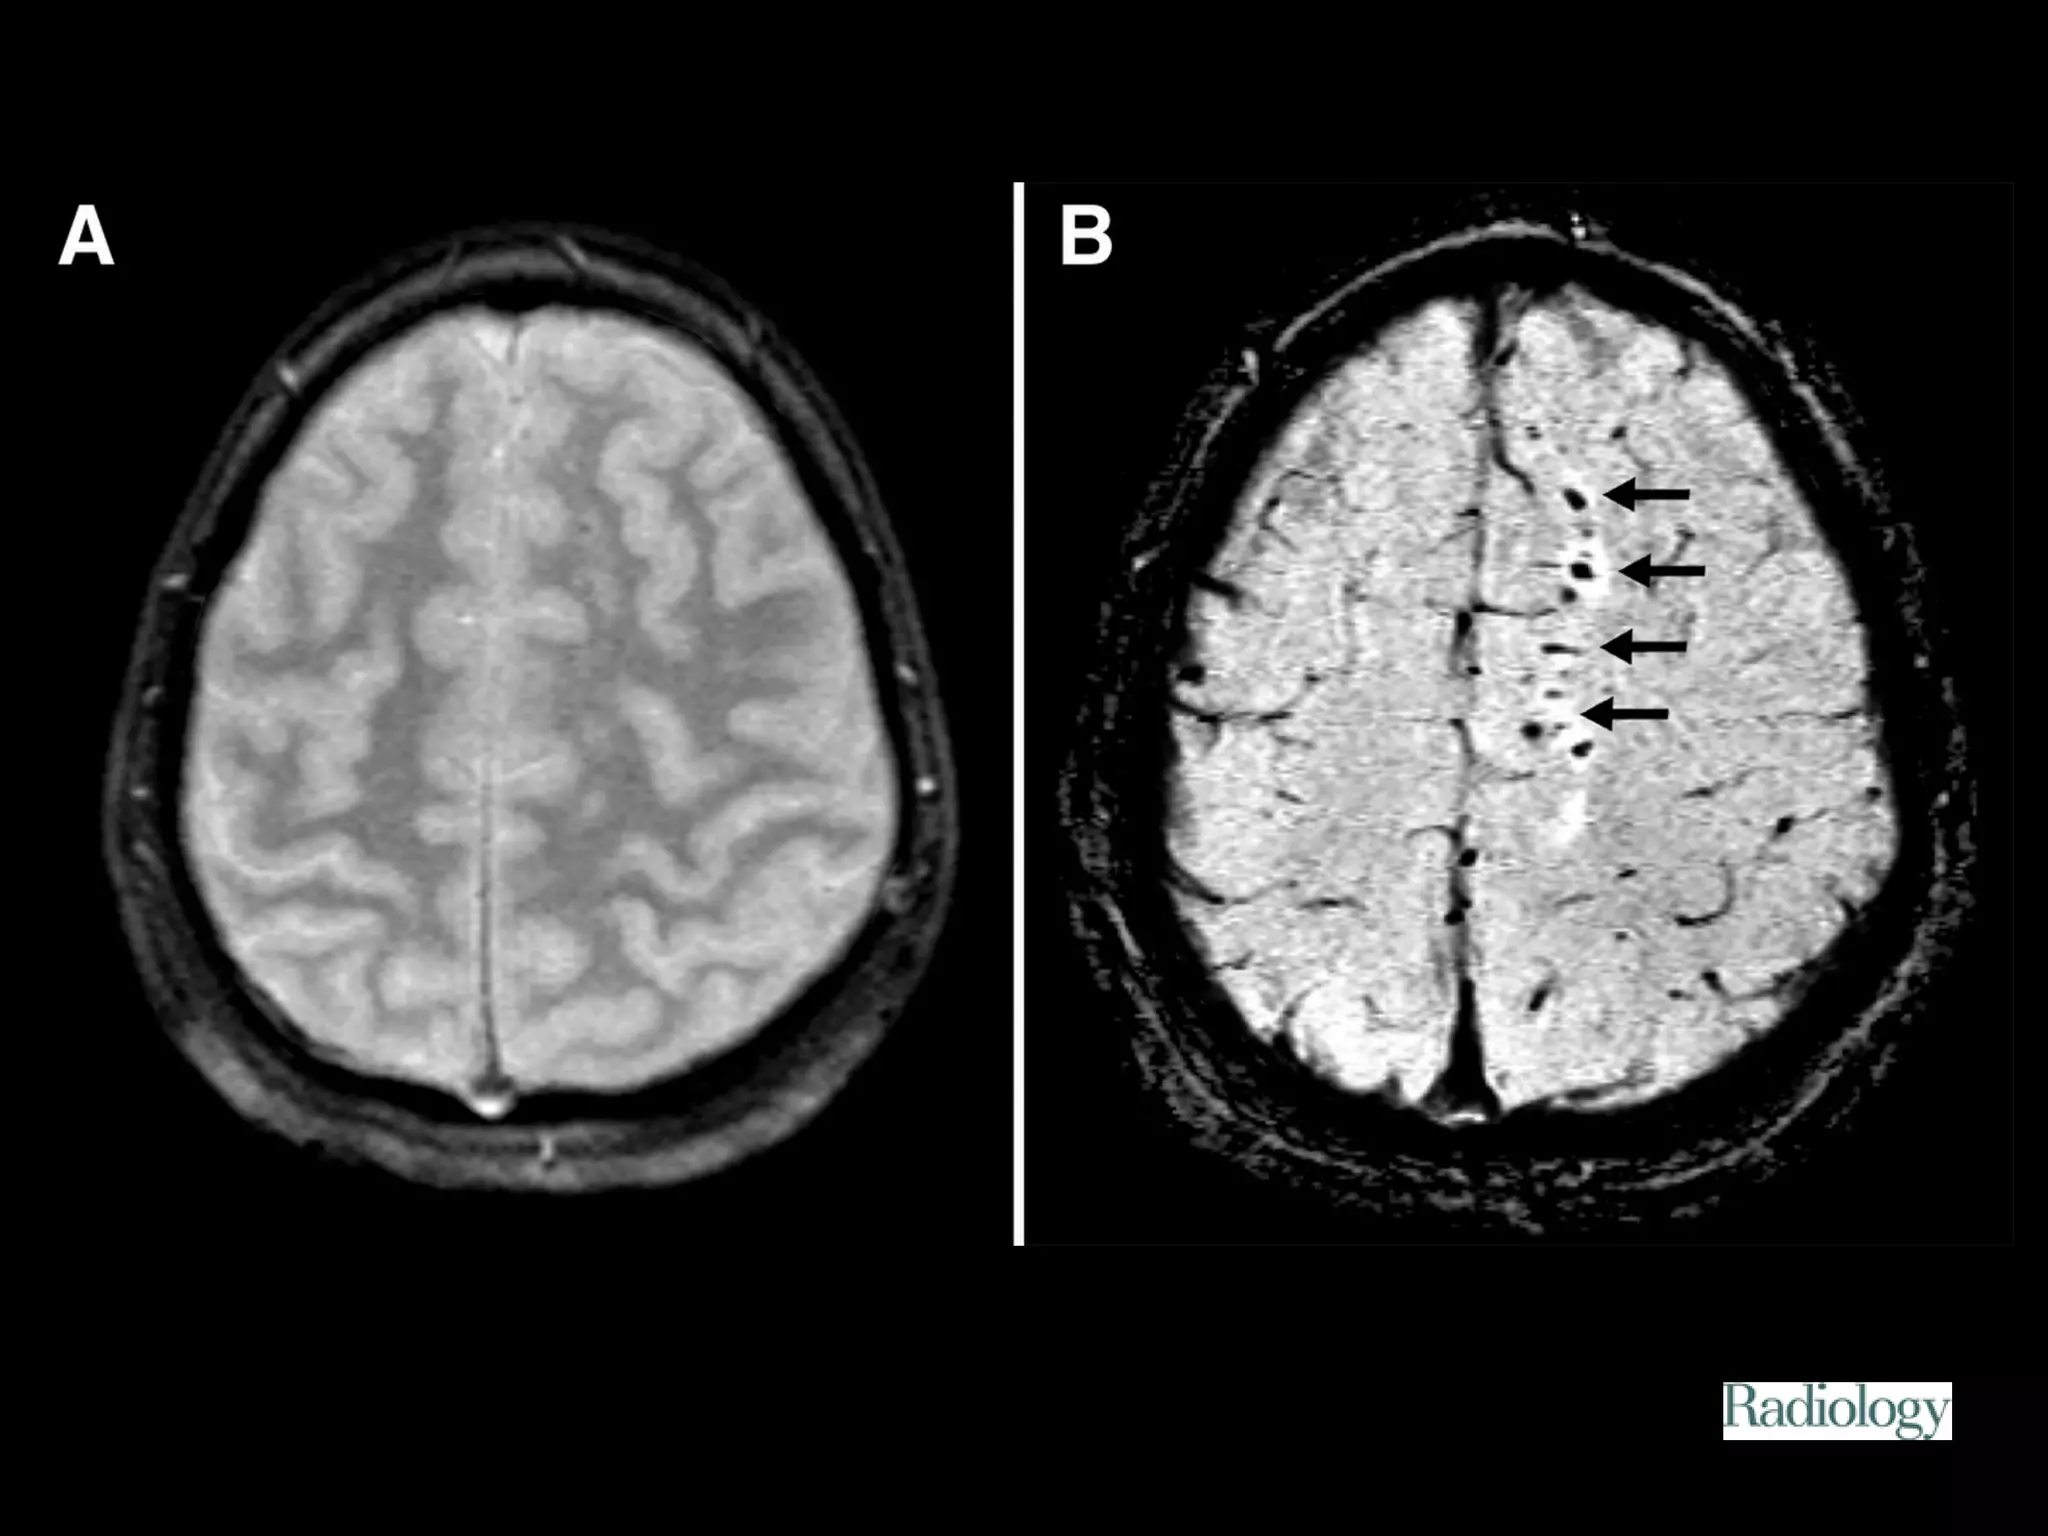

Diffuse axonal injury

Diffuse axonal injury (DAI) is a major form of traumatic

brain injury and is caused by shearing stress primarily in

white matter). Various outcomes are reported (ie, learning

disorders, moderate to severe disability, and vegetative

state) but were unable to correlate the extents of early

injury with the prognoses.

Among patients eventually

proven to have DAI, 50-80%

demonstrate a normal CT scan

upon presentation. Delayed CT

scanning may be helpful in

demonstrating edema or

atrophy, which are later

findings. Small petechial

hemorrhages located at the

gray-white matter junction, as

well as in the corpus callosum

and brainstem, are

characteristic of CT-scan

findings in the acute setting.

The ability to detect DAI by using imaging, whether

the lesions are hemorrhagic or nonhemorrhagic, has

substantially improved with the advent of MRI. MR

imaging has been helpful in defining patterns of

injury in adults with DAI—depicting involvement

predominantly in the frontal white matter, corpus

callosum, brainstem, and diencephalon.

Figure 1. Patient 2.

Tong K A et al. Radiology 2003;227:332-339

©2003 by Radiological Society of North America

Figure 2. Patient 4.